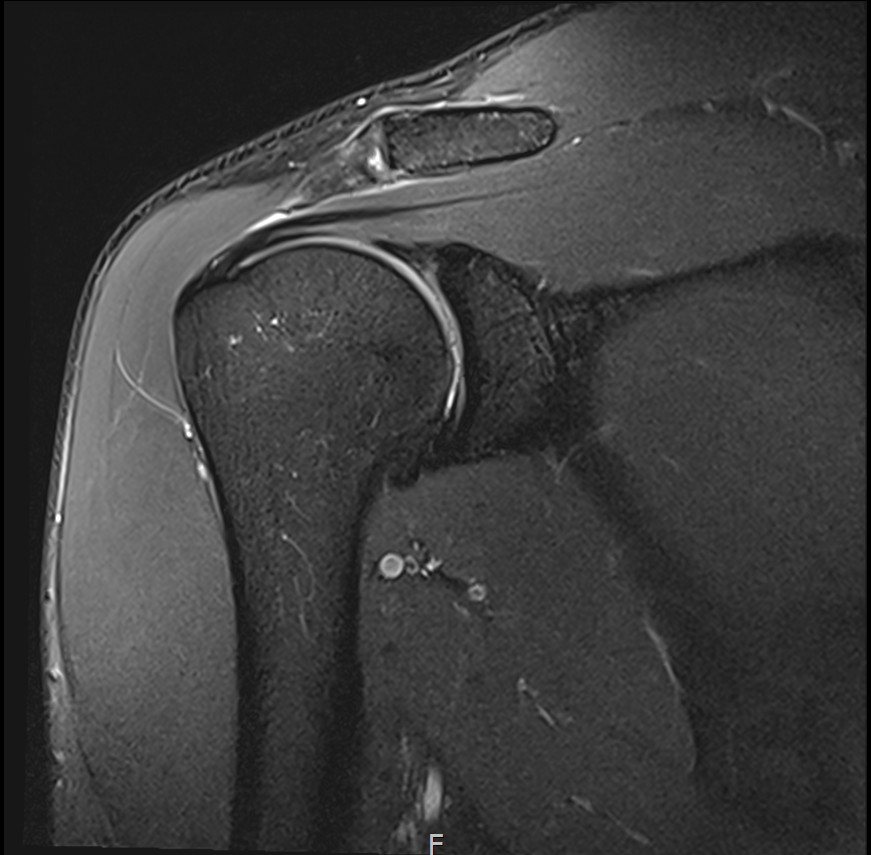

MRI를 검토해보았습니다.

회전근개 극상건의 점액낭면측(bursal-side) 부분파열. 처음보다 파열 범위가 약간 넓어져 있었고, 인대가 얇아진 소견도 보였습니다.

MRI: 극상건 점액낭면측 부분파열

인대 두께: 4.2mm (정상 5~6mm보다 얇음)